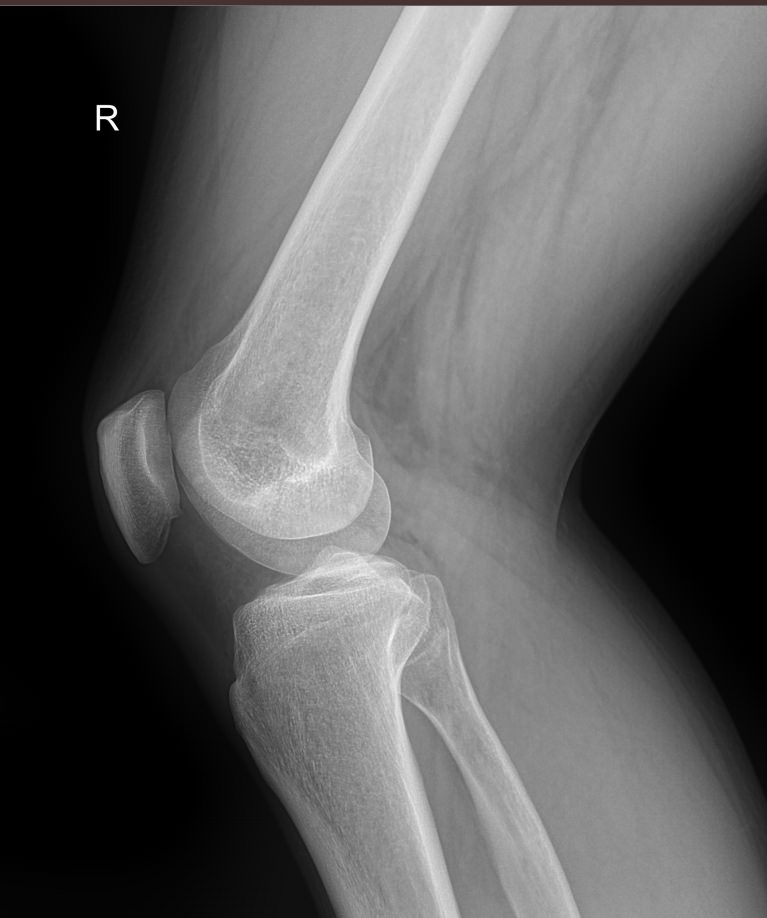

Что покажет рентген обоих коленных суставов в одной проекции

В протоколе у каждого сустава описывается:

• Состояние мягких тканей;

• Суставная щель ― в норме, расширена, сужена, затемнена, имеет дополнительные включения;

• Состояние суставных  поверхностей и их соответствие друг другу ― несоответствие говорит о вывихе;

• Положение надколенника ― обычное или нет;

• Состояние костной ткани и надкостницы ― могут быть обнаружены участки разрежения, размягчения или других патологических процессов, а также свежие и сросшиеся переломы.